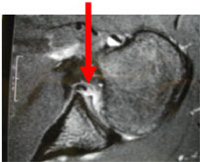

Lors de l’accident, en se déboîtant, la tête arrache le bourrelet vers l’avant et détache la capsule habituellement fixée sur l’os. Une fracture du bord antéro inférieur de la glène peut survenir. L’absence fréquente de cicatrisation de ces lésions favorise alors les récidives, on parle d’instabilité. Plus la première luxation survient tôt, plus le risque de récidive est élevé. Par exemple lorsque la première luxation survient à 20 ans statistiquement le risque de récidive est de 50 %, après 40 ans les récidives sont rares. Les récidives surviennent essentiellement dans les 2 premières années après l’accident. Le traumatisme est de moins en moins important au fil des récidives avec même parfois luxation au cours du sommeil.

Lésion du bourrelet à l’IRM |

Le premier examen à réaliser est la radiographie standard. On pourra apprécier l’existence d’arthrose, d’un bec acromial agressif (frottant sur les tendons) et d’autres signes indirects de tendinites ou de rupture de la coiffe des rotateurs. Pour confirmer le diagnostic de rupture la coiffe des rotateurs, il est nécessaire de réaliser une échographie, un arthroscanner ou une IRM de l’épaule. Ces examens vont confirmer le diagnostic et évaluer la taille et la gravité de la rupture. On pourra alors savoir si la rupture des tendons de la coiffe des rotateurs est réparable ou non.